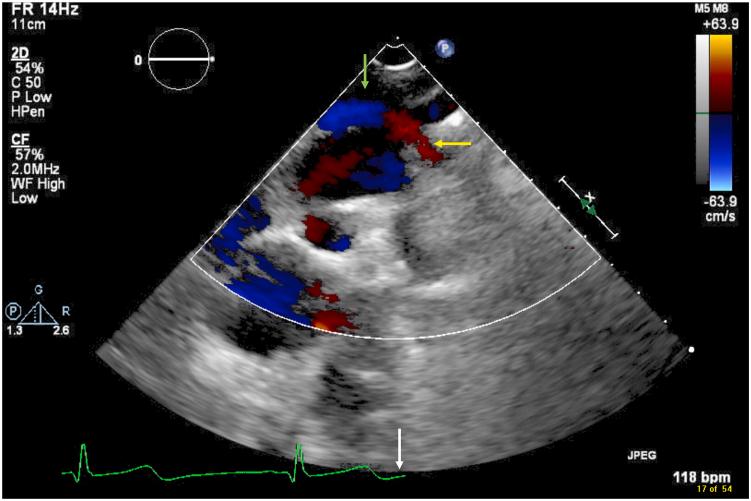

• Most AVFs present with a continuous murmur with radiation to the back. • There is little evidence to guide management of thoracic AVF. • Management options include surgical repair, embolization, or conservative management. • Conservative management is a reasonable approach in asymptomatic patients.